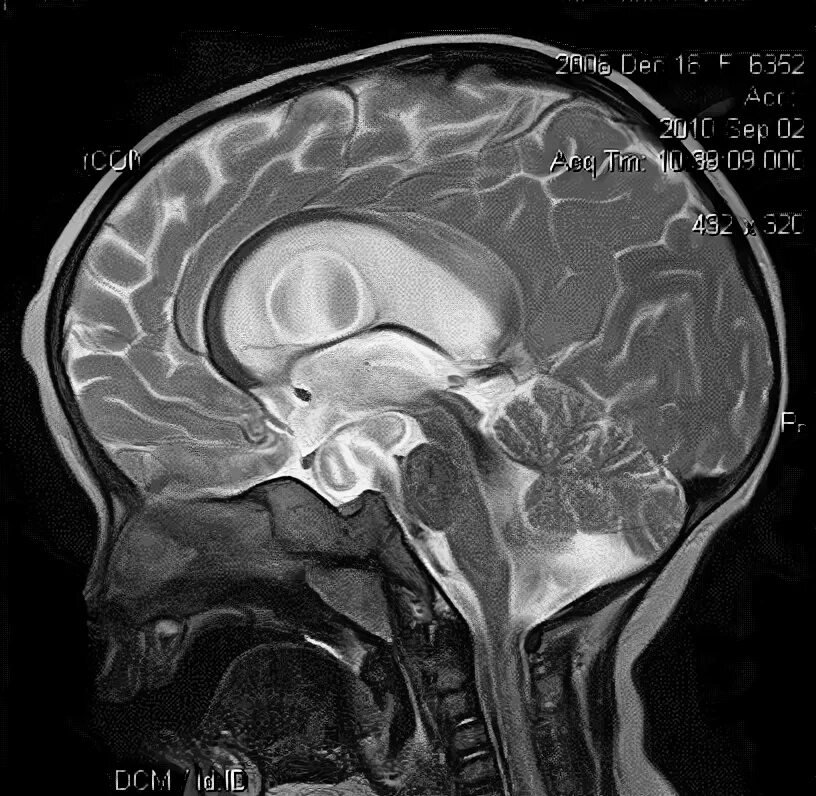

Денди уокера мрт